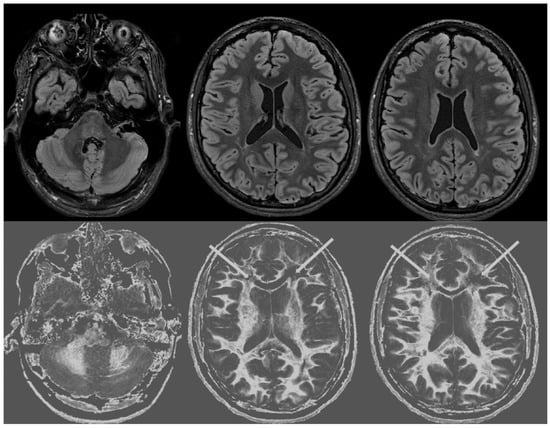

Figure 3 shows narrow mD dSIR images from the normal 18-year-old volunteer. His white matter is normal and shows a low signal (dark) appearance with a mid-grey appearance in and around the corticospinal tracts. Normal high signal boundaries (white lines) are seen at junctions between white and grey matter.

Figure 3. Normal volunteer. Two-dimensional narrow mD dSIR images. The narrow mD dSIR images show normal white matter as a very low signal intensity (dark) except for intermediate areas in and around the corticospinal tracts. Normal high signal boundaries are seen at the junction between white matter and grey matter.